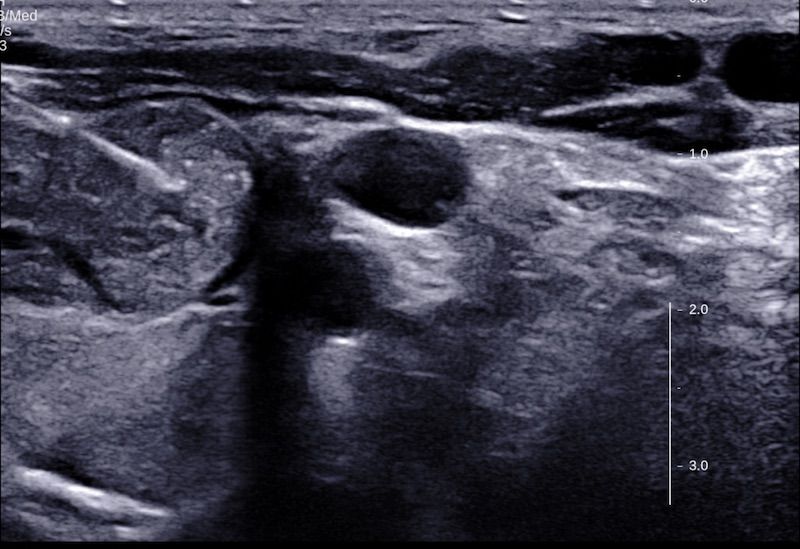

Zapraszam do zapoznania się z relacją filmową z zabiegu leczenia etanolem guzka płynowego tarczycy wraz z opisem metody i wyjaśnieniami. Zabieg został przeprowadzony w Szpitalu na Klinach.

Wykonuję zabiegi leczenia guzków tarczycy małoinwazyjnymi metodami: laserowej termoablacji (EchoLaser) i przezskórnego leczenia etanolem.

Zabiegi oraz badania USG tarczycy oraz biopsji cienkoigłowej celowanej tarczycy (BACC) są wykonywane przy pomocy technik wspomagających, jak elastografia, oraz wizualizacja igły biopsyjnej.

Kolejna moja wizyta związana z leczeniem guza na tarczycy. Zabiegi polegają na ewakuacji płynu i podawaniu stężonego etanolu do guzka, alternatywa to wycięcie płata tarczycy ale Pan doktor walczy i wyjaśnia że to ostateczność. Pan doktor wyjaśnił wszystkie za i przeciw, jest konkretny. Dziękuje Panie Doktorze